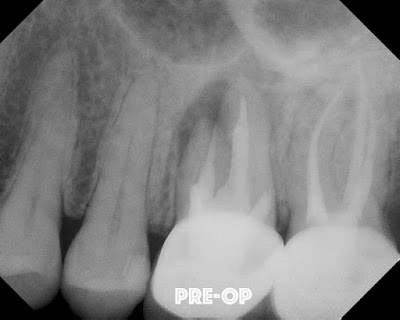

The following case is unique because all three roots of #14 were treated surgically - outside of the mouth.   Traditional surgical access to the palatal root is difficult to impossible from the traditional buccal surgical approach.

This patient came to SSE for RCT in 2010. It was a necrotic and RCT was completed.  The lesion failed to heal, so retreatment was completed in 2012.  Lesion still failed to heal, so intentional replantation was chosen as a last resort before extracting the tooth #14.

Tooth #14 was carefully extracted and all 3 canals were resected, retrofilled and reimplanted within minutes.